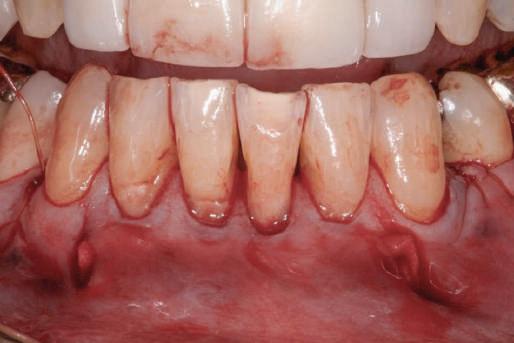

Reprepararea intraorală a bonturilor Acest pacient prezenta dentiţia maxilară compromisă, refuzând proteza mobilizabilă. Prin abordarea în etape, se menţin o parte din bonturile dentare naturale; s-a observat recesie în momentul amprentării pentru cel de-al doilea grup de implanturi.

Fig. 1 prezintă pacientul după inserarea primului set de bonturi implantare individualizate; dinţii naturali adiacenţi

sunt încă prezenţi pentru a susţine puntea provizorie.

Şapte luni mai târziu (fig. 2), acele bonturi individualizate din prima etapă au manifestat semne de recesie de 1-3mm. Atitudine: S-a decis reprepararea intraorală a tuturor bonturilor (fig. 3), astfel încât toate marginile bonturilor să fie la nivelul sau sub marginea gingivală (de notat că 1.1. şi 2.1. au fost submersaţi ulterior pentru a avea sprijin implantar deplin).

Deşi reprepararea a îmbunătăţit marcat estetica finală, a necesitat aplicarea şnurului de retracţie, amprente noi şi turnări noi.

Un caz separat dar similar ilustrează în figurile 4 și 5 reprepararea intraorală a bontului.

Cazul (1): Reprepararea intraorală a bonturilor Figurile

1. Aspect după inserarea primului set de bonturi implantare individualizate.

2. După 7 luni, bonturile individualizate din prima etapă au prezentat recesie de 1-3mm.

3. Bonturile repreparate intraoral.

Alt caz (1) Figurile

4. După osteointegrarea implantului 2.4., s-a observat recesia în etapa de amprentare a implantului 2.5.; s-a decis reprepararea marginilor bontului individualizat CAD/CAM 2.4. Înainte de preparare s-a aplicat şnur de retracţie pentru a evita lezarea ţesutului şi a îmbunătăţi vizibilitatea dintelui 2.3. şi a marginii bontului implantar individualizat. Aşa cum era de aşteptat, recesia a fost mai mare de-a lungul versantului distal al bontului 2.4. adiacent locului de extracţie vindecat/cu implantul mai nou.

5. Bontul individualizat aplicat (2.5.) cu bontul repreparat anterior (2.4.). Nu a survenit recesie nouă de o perioadă de peste 3 ani.